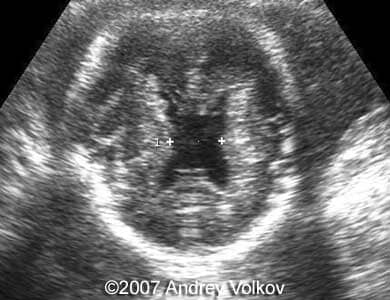

A 26-year old G1P0 from a nonconsanguineous couple (husband 35 years old), with noncontributive history, presented to our unit at 30 weeks of pregnancy. Our ultrasound examination revealed following findings:

• Lobar holoprosencephaly;

Images 1, 2: 30 weeks of pregnancy; Image 1 shows cloverleaf shaped fetal skull. Image 2 shows transverse scan through the fetal skull with lobar holoprosencephaly.